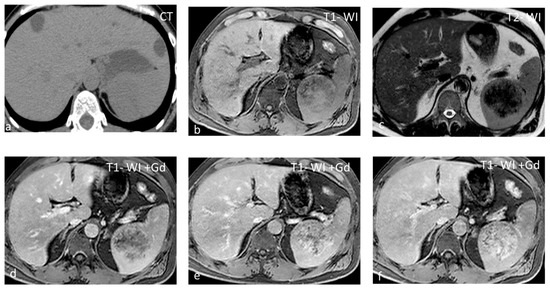

Sarcoidosis is a multisystem disease characterized by the presence of non-caseating granulomas. One-third of patients presenting with splenic sarcoidosis findings have normal chest radiography [18]. Splenic involvement has been reported in about 40% of cases of multisystem sarcoidosis, but isolated sarcoidosis of the spleen is extremely rare [19]. It may present either as splenomegaly or with multiple nodules, whereas a solitary splenic lesion is very rare. Patients with diffuse splenic granulomas have a worse prognosis in terms of persistent chronic sarcoidosis than patients without splenic involvement or patients with limited splenic disease [20]. Nodules appear hypodense on CT and have low SI both on T1-WI and T2-WI, with minimal delayed enhancement [21] (Figure 2). Nodules are best seen on T2-WI with fat saturation and on early gadolinium-enhanced T1–WI. MRI is said to be able to monitor disease activity, as during active inflammation, nodules demonstrate T2-WI hyperintensity due to edema and high vascular permeability, as well as restricted diffusion [22]. The main differential diagnosis includes infections, especially tuberculosis, and malignancies, especially lymphoma. The final diagnosis is based on three main criteria: a compatible presentation, the evidence of non-caseating granulomas on histological examination, and the exclusion of any alternative diagnosis [23].

Figure 2.

Sarcoidosis. US shows multiple hypoechoic nodules (a). The nodules appear slightly hypointense on T2 WI (b) and show mild delayed enhancement (c,d).